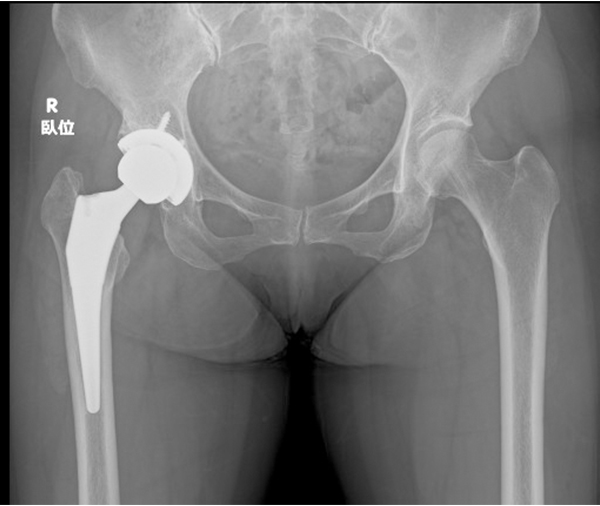

Q.「人工股関節置換術」について教えてください

人工股関節は金属製(コバルトやチタン合金)のステムとソケット、ポリエチレン製のライナー、セラミック製の骨頭で構成されています。 当院ではライナーに耐摩耗性に優れた超高分子ポリエチレンを使用しています。また、接着剤として骨セメントを使用するタイプと使用しないタイプがあり、当院では原則セメントを使用しないタイプを採用しています。

MIS人工股関節置換術

MISとはminimally invasive surgery(最小侵襲手術)という意味です。当院ではMISの一つ、仰臥位前外側進入法(ALS-Approach)を採用しています。 従来法では15~20cmの皮膚切開が必要でしたが、MISでは8~12cmで行うことが可能です(変形の程度、体格により適応とならない場合があります)。 また、股関節周囲の筋肉・腱を切らずに手術を行うことで、術後の痛みや筋力低下が軽減され、早期リハビリ、早期退院、早期社会復帰が可能となりました。多くの患者様が術後2週間程度で退院され、入院医療費負担の軽減にもつながります。

仰臥位で行うため、左右の股関節が傷んでいる場合の両側同時人工股関節手術にも対応可能です。